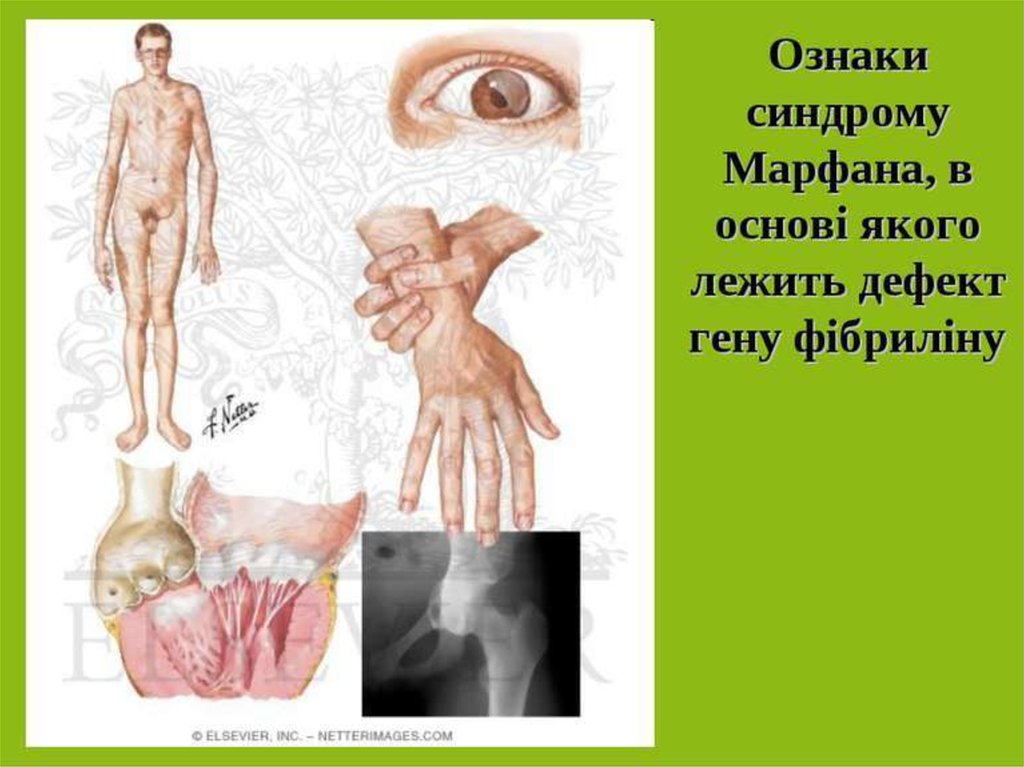

Sindrom marfana tema nauchnoj stati po klinicheskoj medicine chitajte besplatno tekst nauchno issledovatelskoj raboty v elektronnoj biblioteke kiberleninka (Тип файлу jpg)

Sindrom Marfana Tema Nauchnoj Stati Po Klinicheskoj Medicine Chitajte Besplatno Tekst Nauchno Issledovatelskoj Raboty V Elektronnoj Biblioteke Kiberleninka

Sindrom marfana tema nauchnoj stati po klinicheskoj medicine chitajte besplatno tekst nauchno issledovatelskoj raboty v elektronnoj biblioteke kiberleninka (Тип файлу jpg)

Sindrom Marfana Tema Nauchnoj Stati Po Klinicheskoj Medicine Chitajte Besplatno Tekst Nauchno Issledovatelskoj Raboty V Elektronnoj Biblioteke Kiberleninka